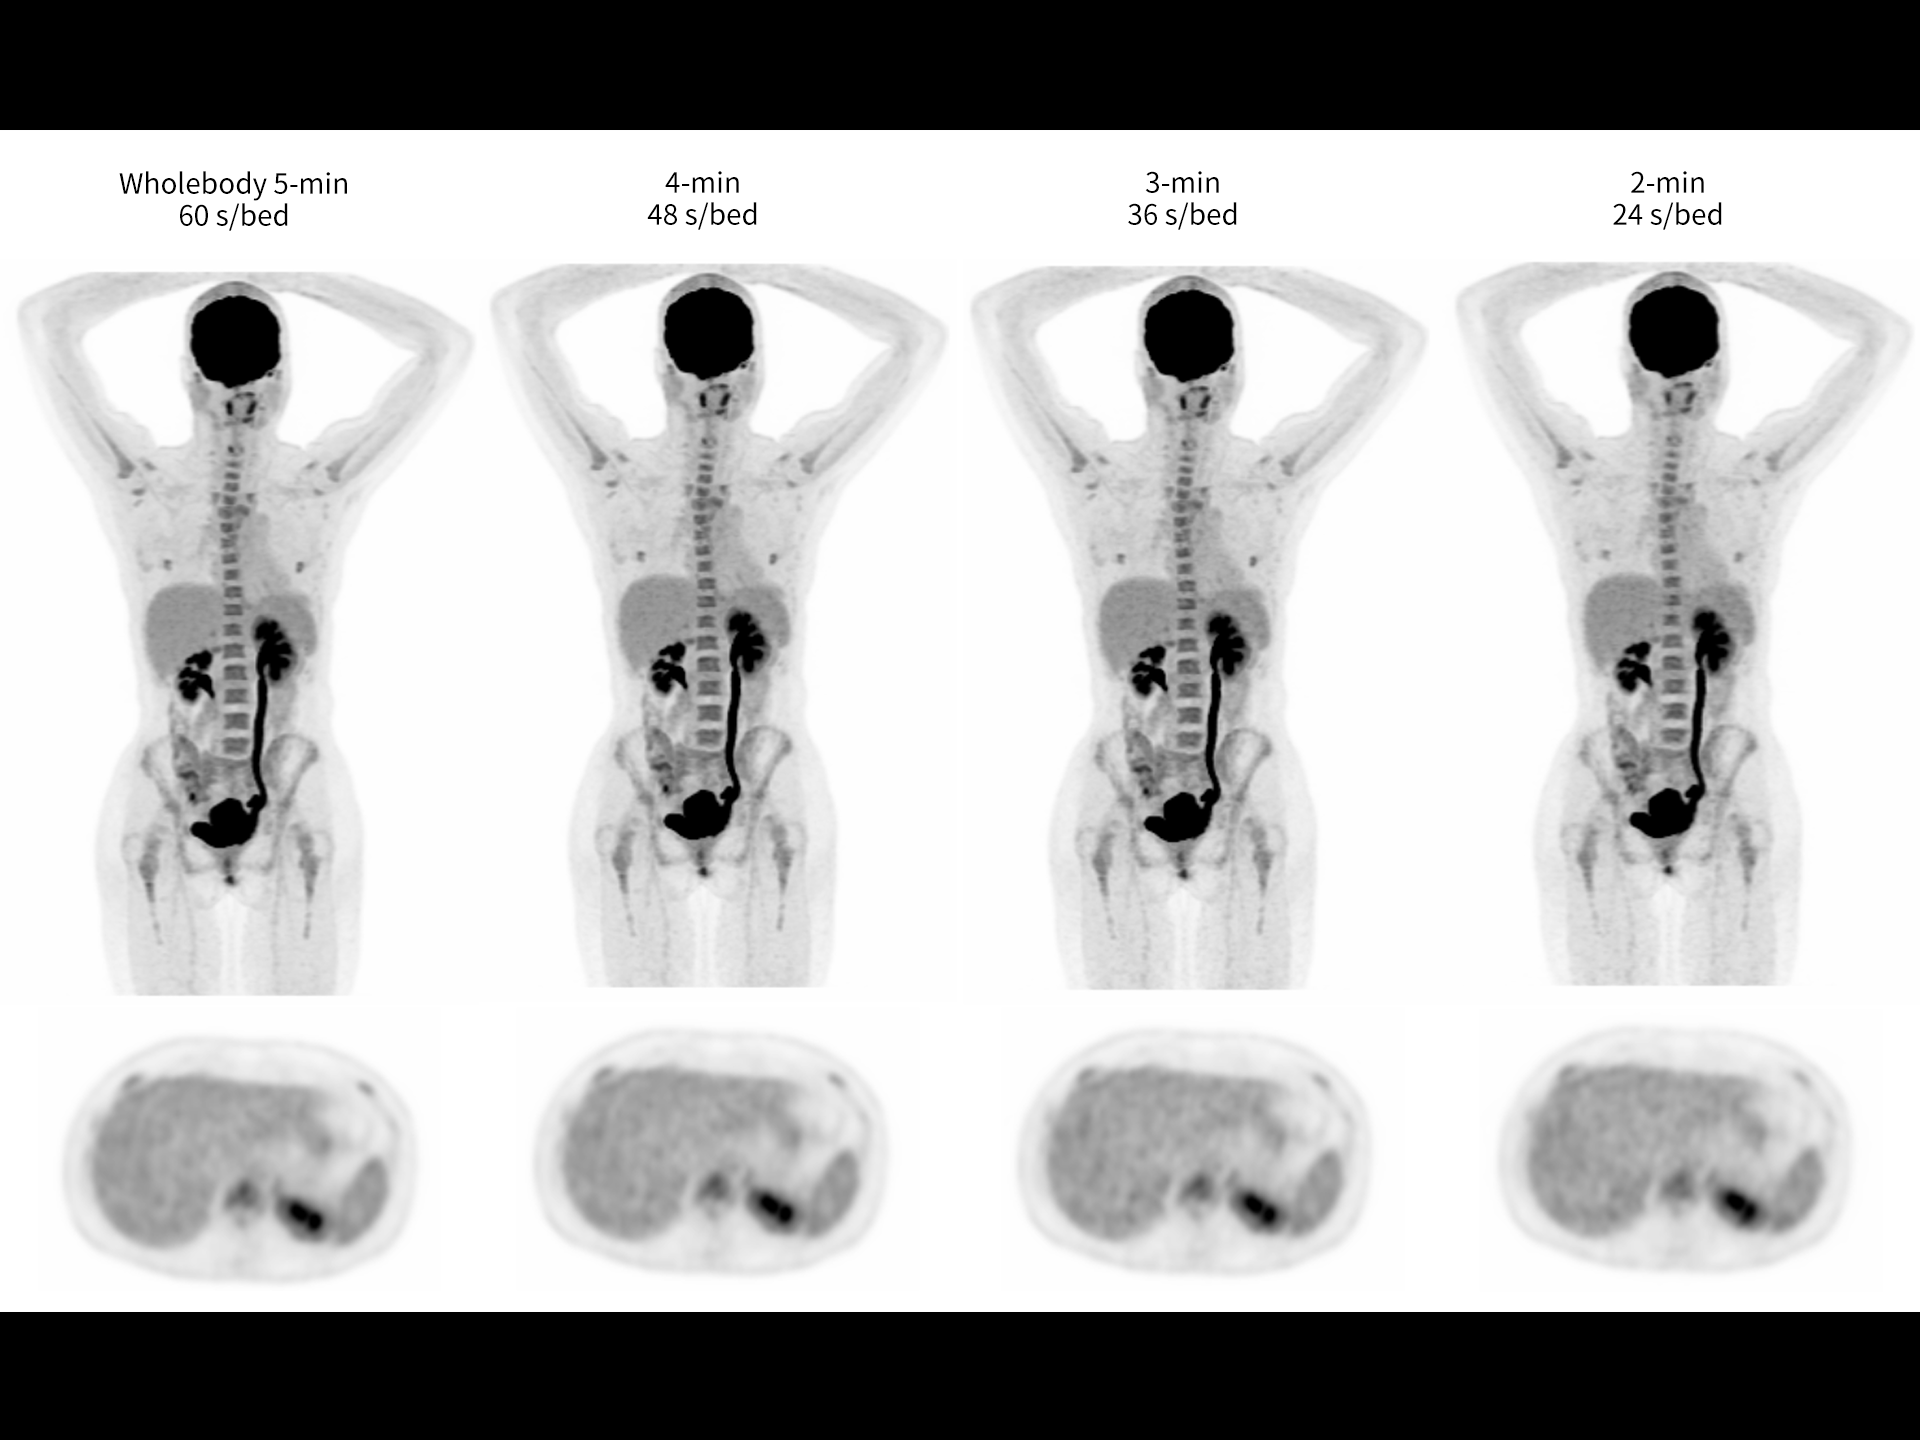

Fast whole-body PET/CT down to 2 minutes*

*Images Courtesy of Pueblo Medical Imaging